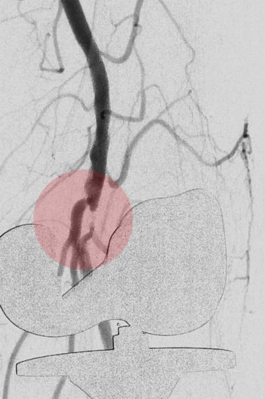

5. Thrombektomie – mechanische Entfernung von Blutgerinnseln

Wenn ein Gefäß durch Blutgerinnsel verschlossen ist, kann man den Verschluss mechanisch wiedereröffnen, indem man die Ablagerungen über spezielle Katheter absaugt. Dazu stehen uns Kathetersysteme, die mit Vakuum arbeiten bzw. zusätzlich die Gerinnsel vor dem Absaugen mit Hilfe von Wasserstrahlen oder Rotation der Katheterspitze zerkleinern, zur Verfügung.